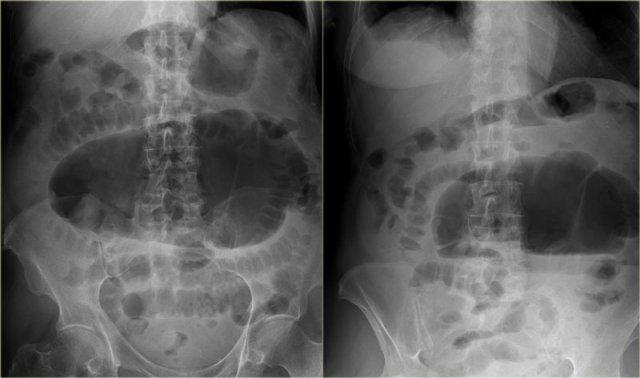

Bên trái là hình ảnh X-quang bụng thẳng của một nam bệnh nhân 57 tuổi với tiền sử đau bụng và chướng bụng tăng dần trong hai ngày.

Hãy quan sát hình ảnh trước rồi tiếp tục.

Ngoài hình ảnh giãn ruột lan tỏa, dấu hiệu chính trên phim này là một cấu trúc chứa khí lớn ở vùng chậu.

Chẩn đoán quan trọng cần nghĩ đến là xoắn đại tràng, và nhiều người sẽ chẩn đoán đây là xoắn đại tràng sigma do vị trí nằm ở vùng chậu.

Tuy nhiên, đây thực chất là xoắn manh tràng như sẽ được giải thích bên dưới.

Các hình X-quang cho thấy hình ảnh điển hình của xoắn manh tràng.

Lưu ý rằng quai ruột giãn hướng về phía vùng xoắn, đây là vị trí mà manh tràng thường nằm.

X-quang bụng tư thế nằm ngửa và đứng thẳng cho thấy dấu hiệu hạt cà phê đặc trưng trong xoắn đại tràng sigma.

Lưu ý rằng các quai ruột giãn hướng về phía vùng đại tràng sigma.

Trên X-quang bụng, rất khó nhận biết tình trạng bệnh lý vì có quá nhiều quai ruột giãn.